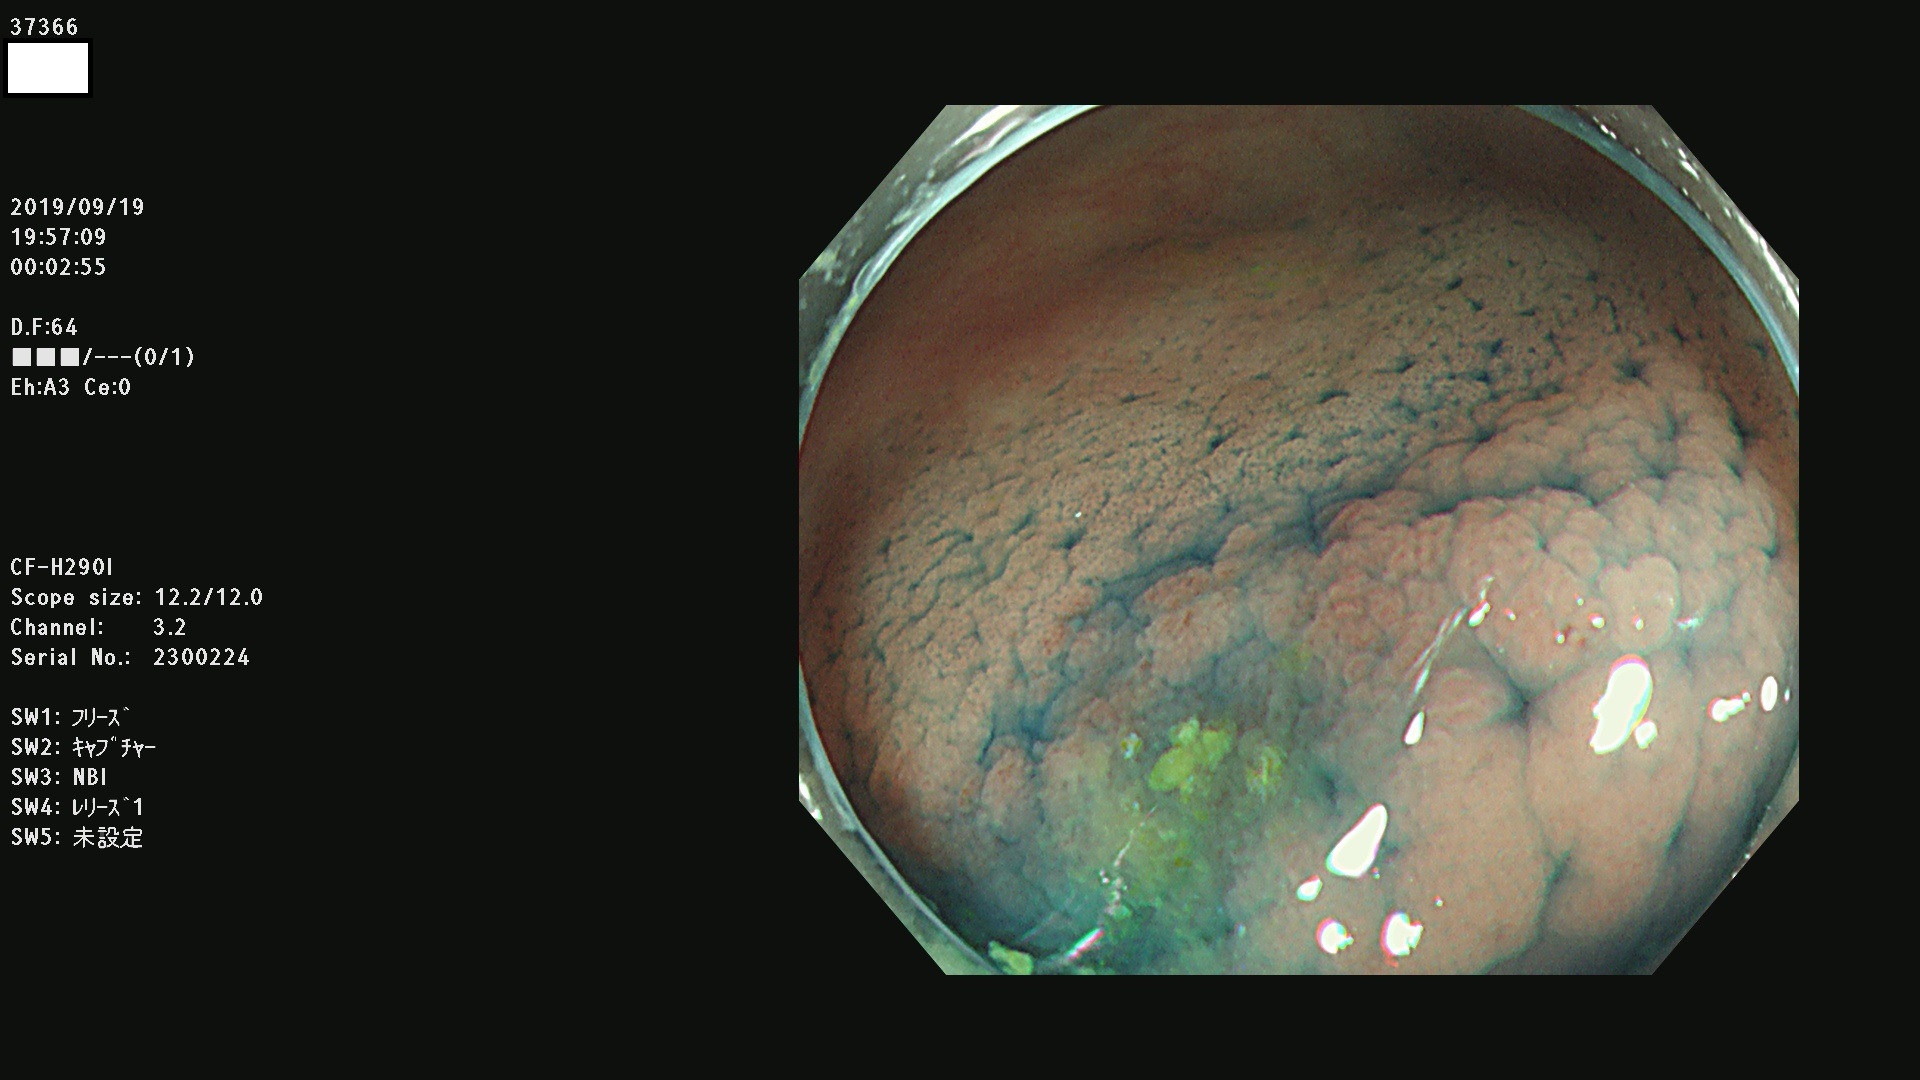

37300(SSAPのみ) 37301 37303 37304 37306 37307 37308 37309 37312 37313 37315(SSAPのみ) 37316 37317(SSAPのみ) 37319 37321(SSAPのみ) 37322 37323 37324 37325 37326 37328(SSAPのみ) 37329 37330 37331 37332(SSAPのみ) 37333 37334 37336 37337 37338 37340 37342 37343(SSAPのみ) 37344 37345 37346 37347 37348 37352(SSAPのみ) 37353 37354 37355 37356 37358 37360 37361(SSAPのみ) 37362 37363 37366 37367 37369 37370 37371 37372(SSAPのみ) 37375 37376 37377 37380 37381(SSAPのみ) 37382 37383 37384 37385(SSAPのみ) 37386 37387 37388 37389 37390 37392(SSAPのみ) 37393 37394 37395 37396(SSAPのみ) 37397 37398(SSAPのみ) 37399

発見困難で危険性の高い平坦型病変(上記100名より抽出) )